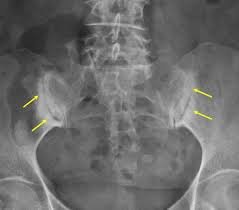

كيف يتم تشخيص التهاب المفصل العجزي الحرقفي؟

يعتمد التشخيص على التقييم السريري الدقيق من قبل طبيب متخصص. ثم مراجعة التاريخ المرضي وطبيعة الألم. وقد يشمل التشخيص:

- فحوصات تصويرية لتقييم حالة المفصل واستبعاد أسباب أخرى لآلام أسفل الظهر.

- استخدام وسائل تشخيصية دقيقة لتحديد مصدر الألم بدقة.

- في بعض الحالات، قد يتم اللجوء إلى حقن تشخيصية للمساعدة في تأكيد أن المفصل العجزي الحرقفي هو السبب الرئيسي للأعراض.